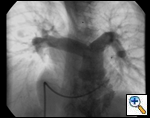

An asymptomatic, 5-year-old, 18-kg boy known by genetic testing to have Williams syndrome on physical examination had a IV/VI harsh systolic ejection murmur and no diastolic murmur. Preoperative echocardiogram showed an aortic root dimension of 2 cm and the dimension at the level of stenosis in the ascending aorta was 8 mm. Peak echocardiogram gradient was 70 mm Hg with a cardiac catheterization gradient of 50 mm Hg. The child had no peripheral pulmonary artery stenosis.

Preoperative transesophageal echocardiogram in long-axis view shows ascending aorta with aortic valve to the left. The markers indicate the aoritc root dimension to be 2.0 cm and hte mid portion of the stenosis to be 0.8 cm.